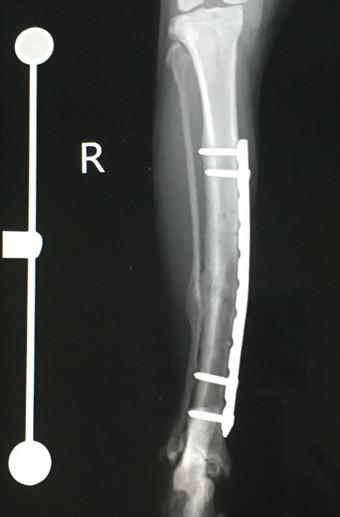

6月3日 手術から 11ヶ月 後

札幌病院、経過観察、骨形成OK

7月に残りのプレート抜去予定